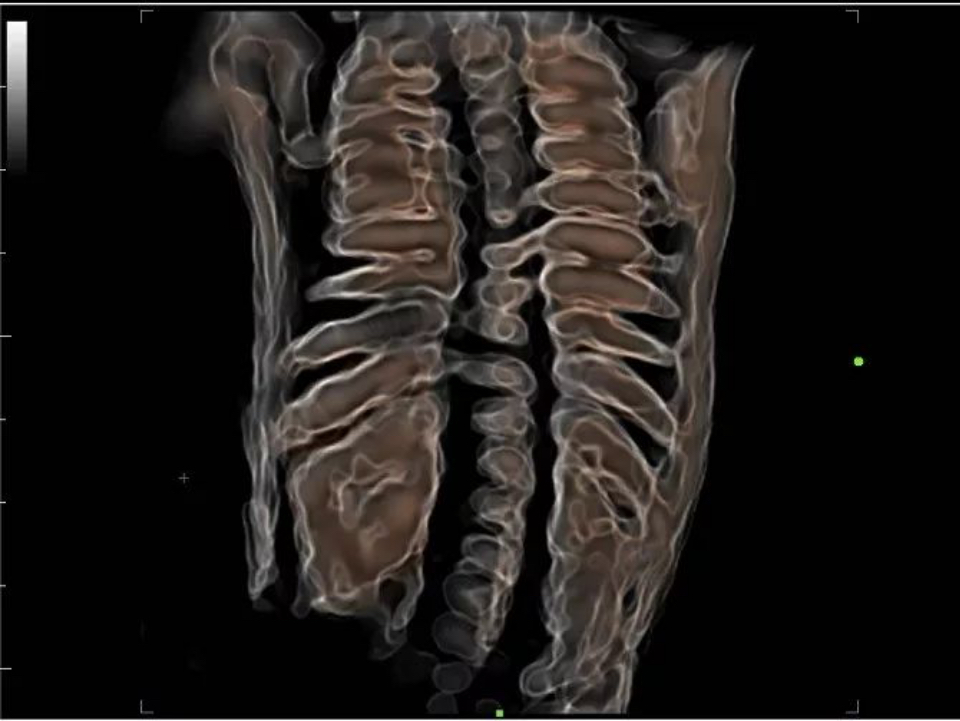

Apart from the speedy hardware structure and premier transducers, X-Insight also significantly optimizes its software to improve scanning efficiency by upgrading iLive to Hyaline — a new rendering method that dynamically applies transparency to rendered structures for a more comprehensive view of anatomy, therefore better displaying internal anatomy from a solid surface. It remarkably improves the detail resolution as well as the anatomical realism of the images.

Fetal spine with Hyaline